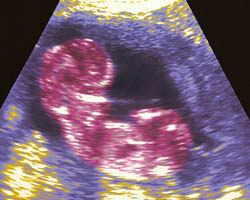

Em seguida poderás ver uma ecografia de 8 semanas, bem como um fantástico vídeo, no qual poderás ver o embrião em movimento. Não percas esta maravilha!

Ecografia de 8 semanas